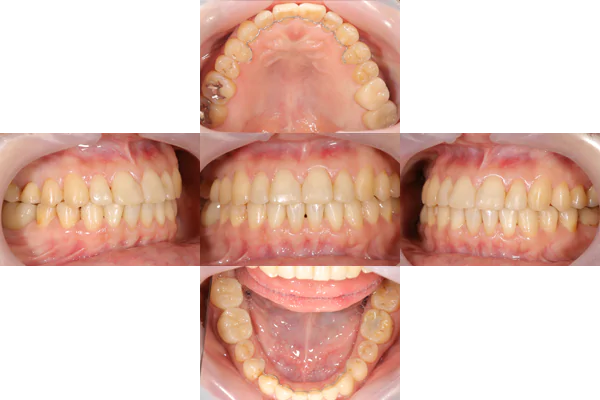

治療前

治療後